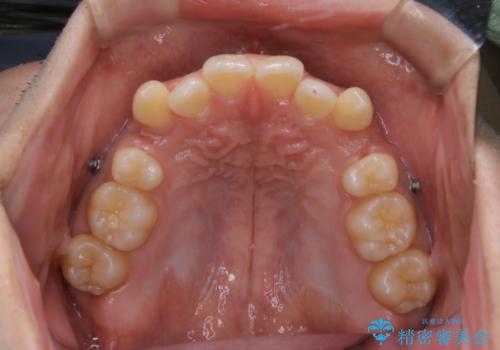

- インビザラインFULL

- 3年

- 治療計画

1日20時間以上、正しくインビザラインを使用して頂いたおかげで、ワイヤーに切り替えることなく矯正治療を終了することが出来ました。周囲からも歯並びがすごく綺麗になったと言われたのことで大変ご満足いただけました。